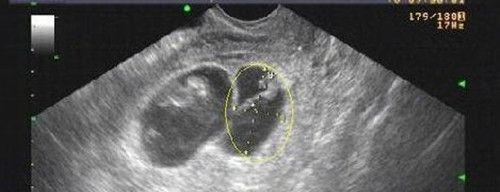

孕囊大小与孕周正常值的图片(孕45天等于孕6周多3天)

怀孕45天的时候,孕囊的平均直径大约在1.5cm左右,这时如果查血HCG值,大约在16000mIU/ml左右。孕妇在停经之后,体内雌激素、孕激素、绒毛膜促性腺激素水平都会增加。

怀孕45天的时候,差不多应当是15毫米左右正常情况下怀孕,最迟第七周就可以发现胎心的波动,如果并没有看到胎心搏动,而妊娠囊又比较小,那么重要考虑胚胎停育的可能。